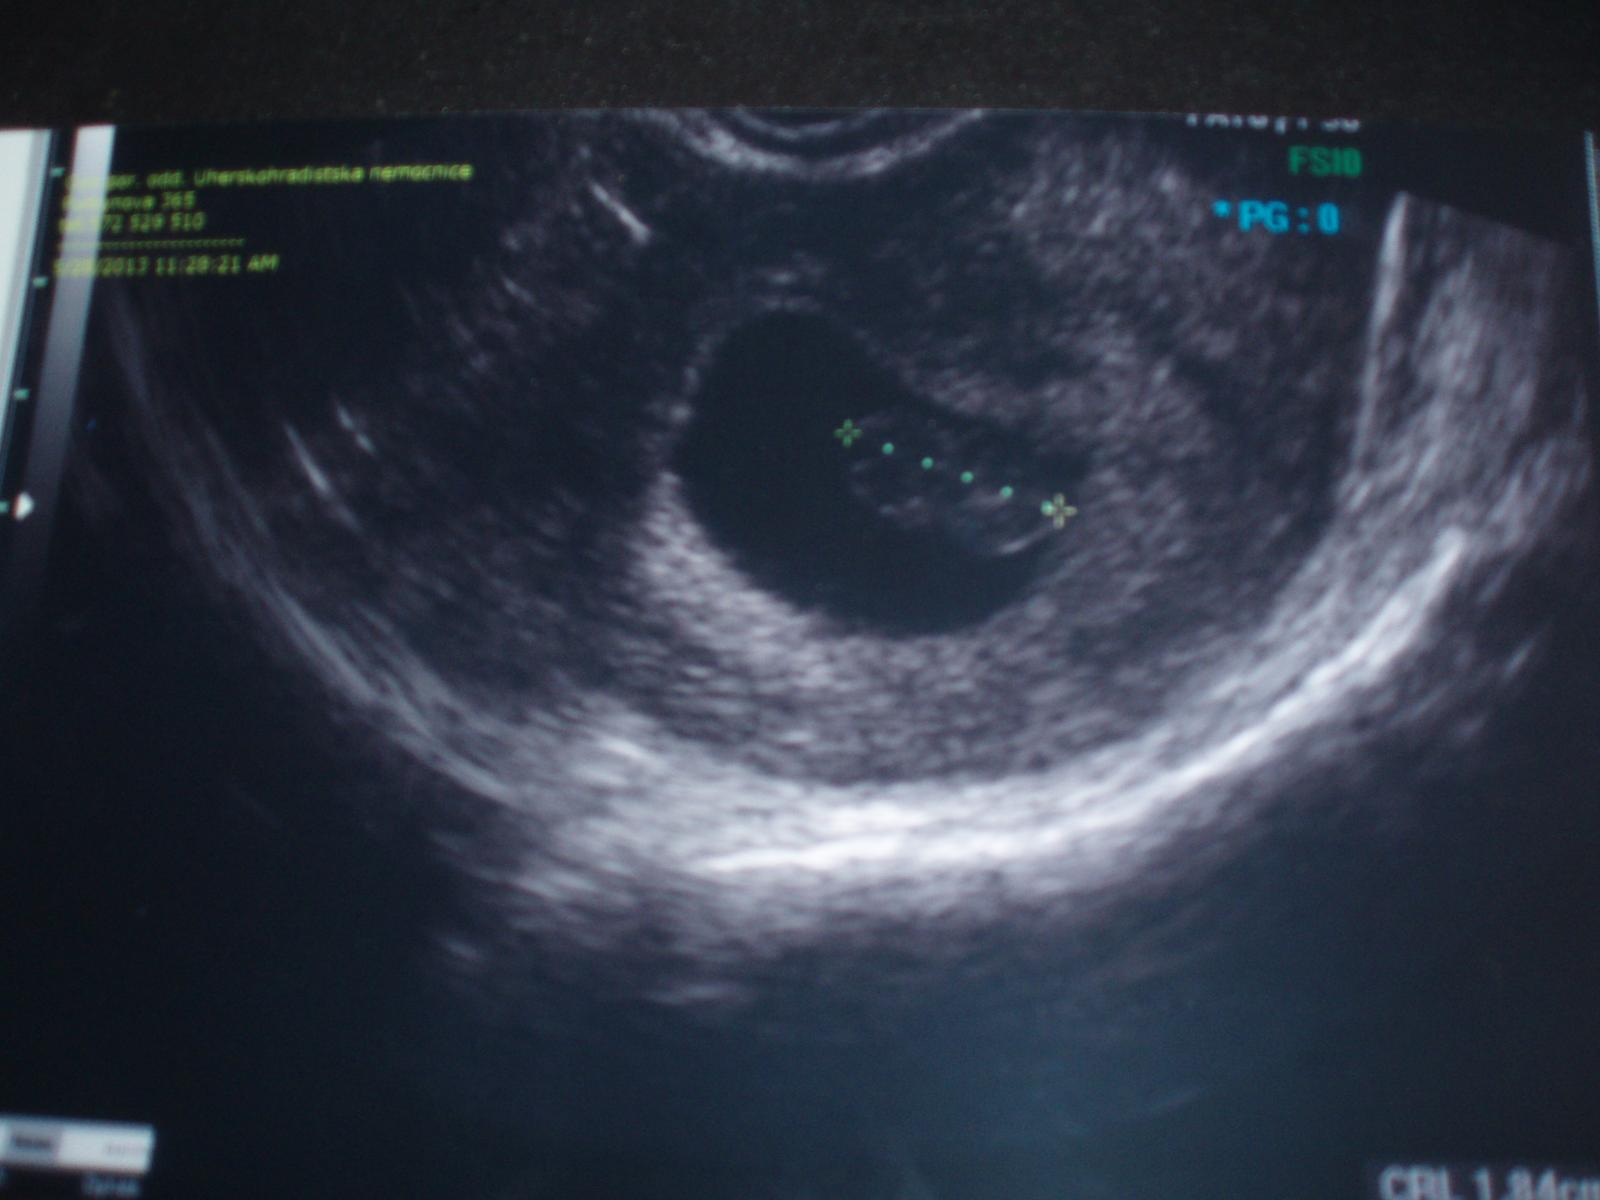

Čau miláčci, tak mám i fotku ( byla jsem ještě nakoupit 🙂 ) malý má 1,82 cm - souhlasí s PM 8+2 tt, srdíčko náádherné - fotku dodám později. děkuji za držení palečků 🙂

Tak tady je 🙂